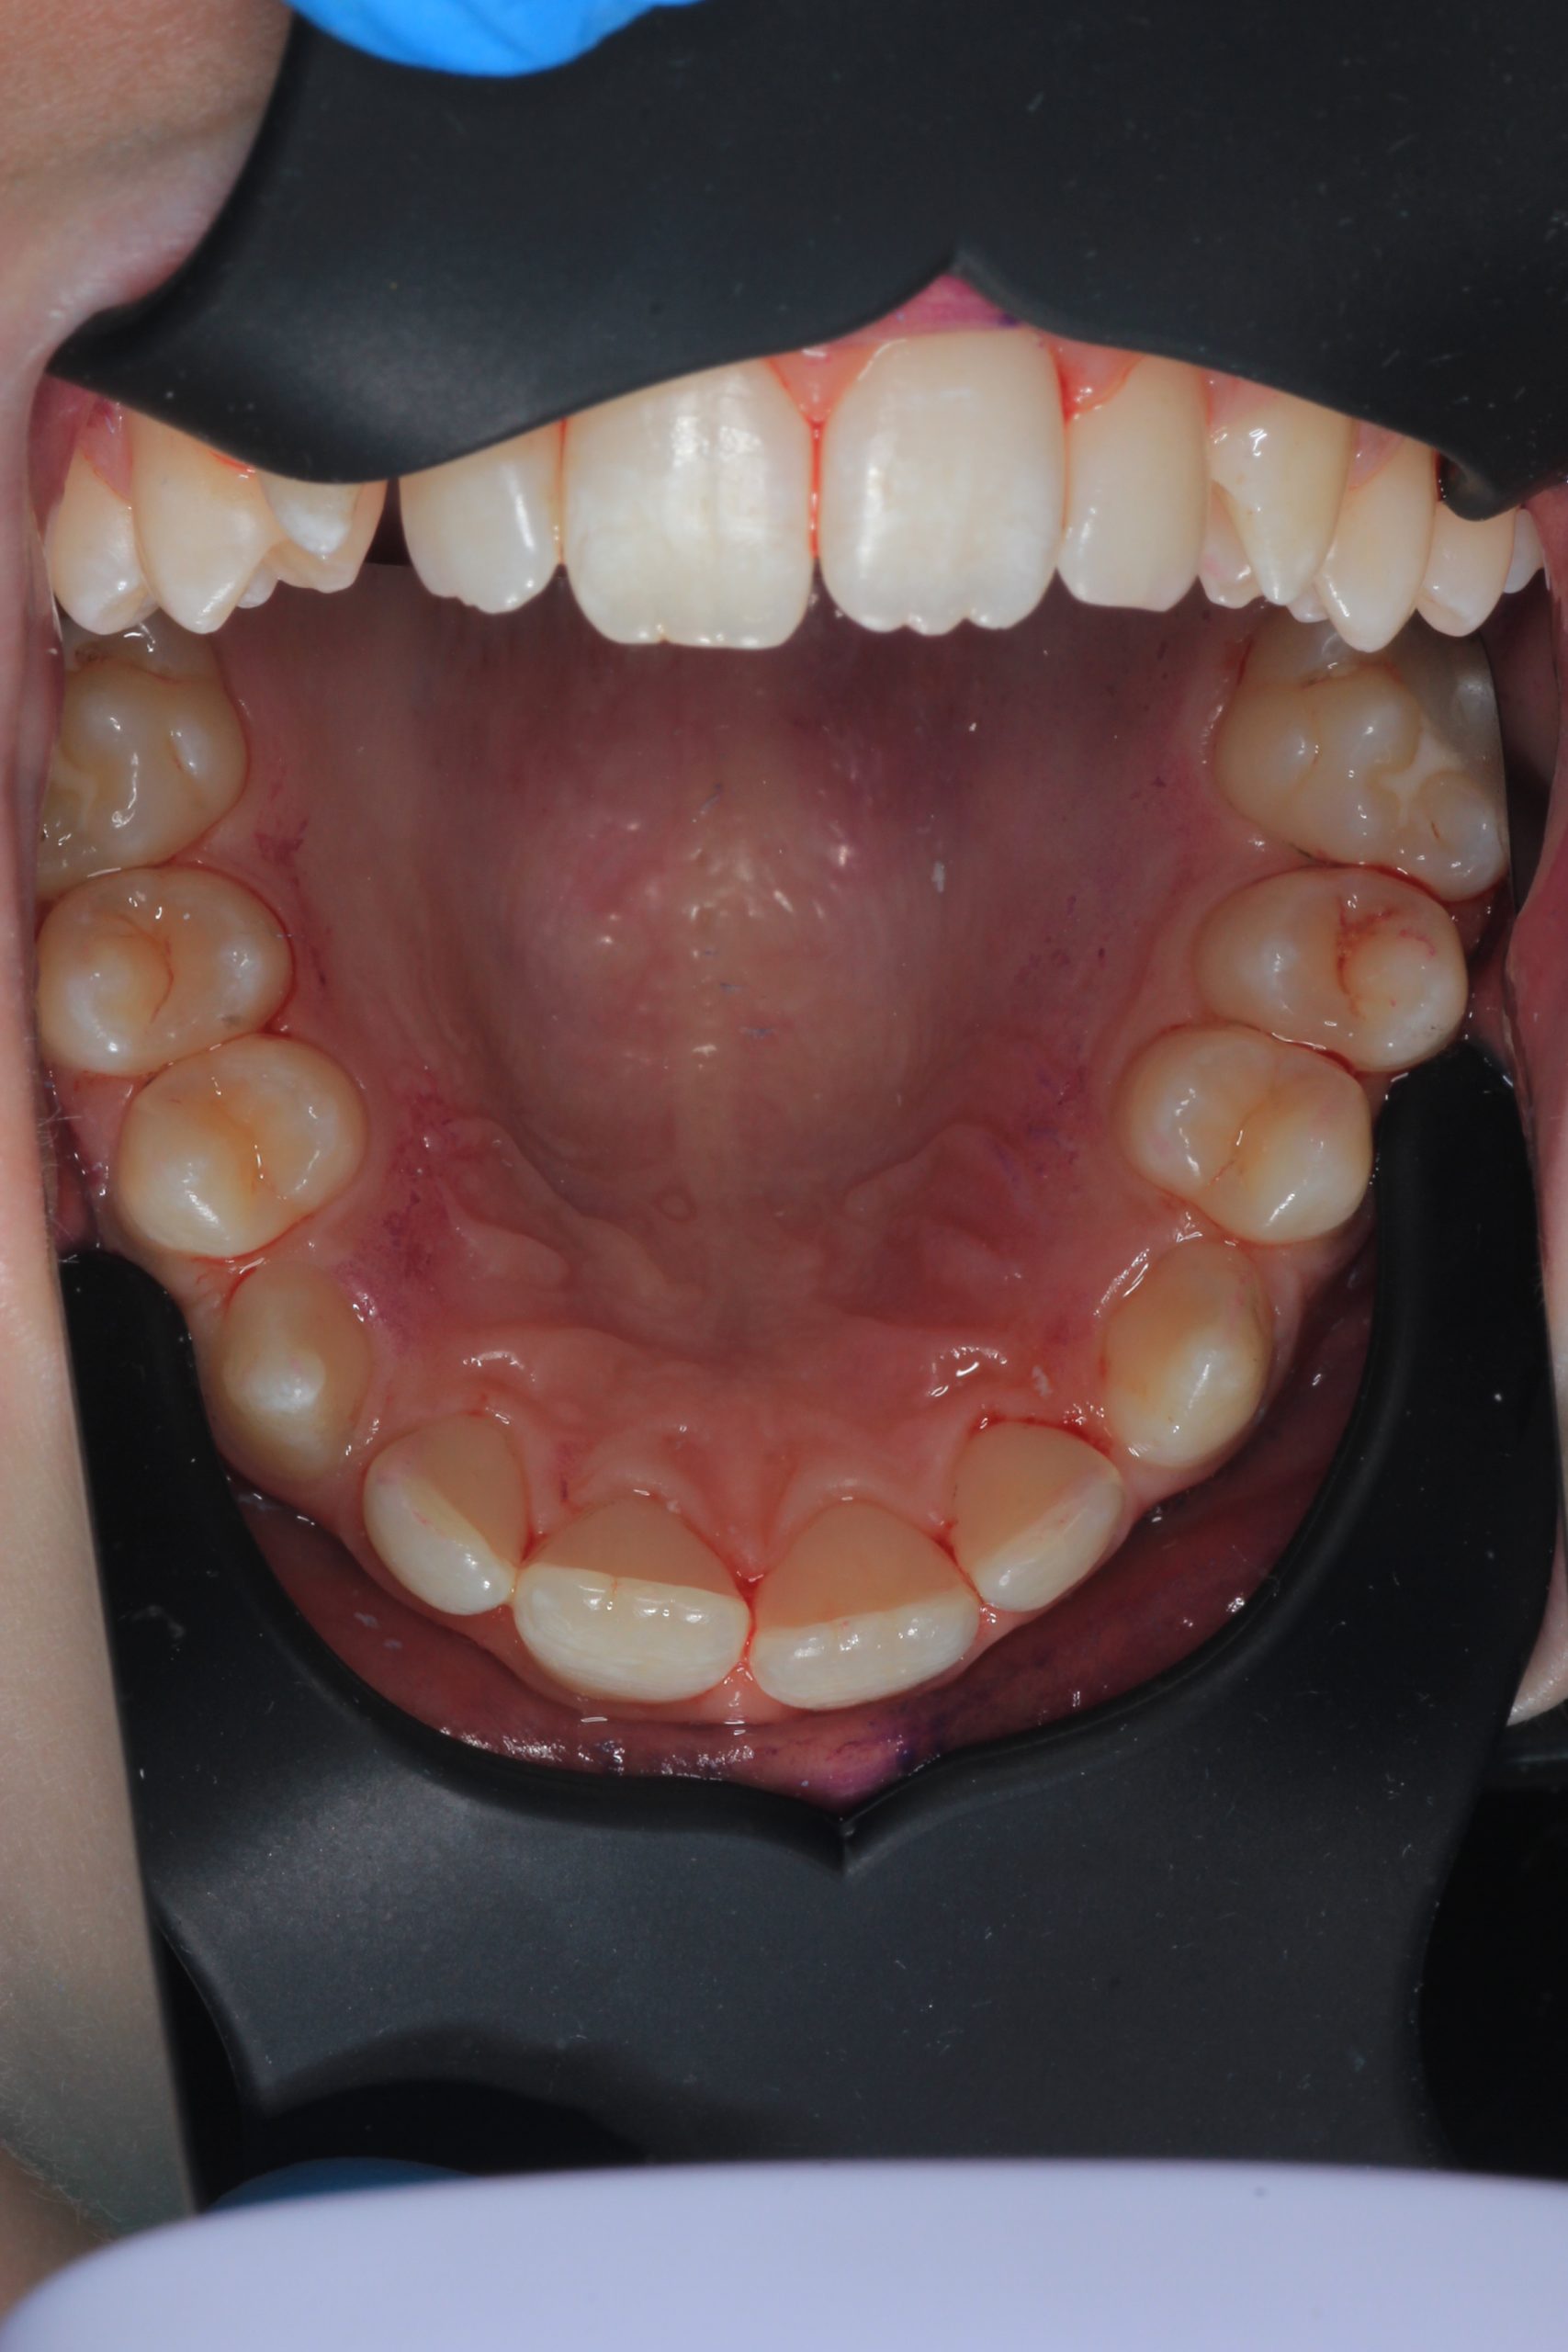

We examine the condition of teeth, gums, and bite. - Plaque Disclosure with Special Indicators

Areas that weren’t cleaned well appear purple. The darker the shade, the older the plaque. This helps both kids and parents understand where brushing needs to improve. - Brushing Training & Home Care Tools Selection